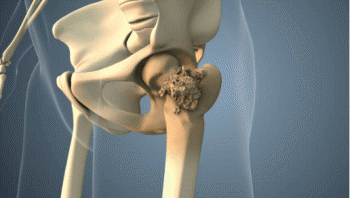

골괴사(뼈 무혈성 괴사)란?

골괴사는 뼈에 공급되는 혈액이 차단되어 뼈 조직이 점점 죽어가는 질환입니다. 주로 대퇴골두(허벅지 뼈 머리 부위), 팔 위쪽, 어깨, 무릎 등에서 발생하며, 모든 연령층에서 발병할 수 있습니다.